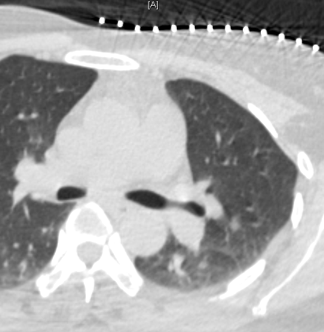

Pulmonary Nodule

CT image Pulmonary nodule before MWA

Primary lung cancer, preoperative examination

CT image of pulmonary nodule during MWA

CT-guided microwave ablation